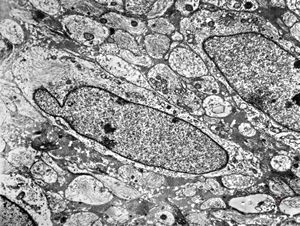

F,44y. | ependymoma

F,44y. | ependymoma

F,44y. | ependymoma

F,44y. | ependymoma